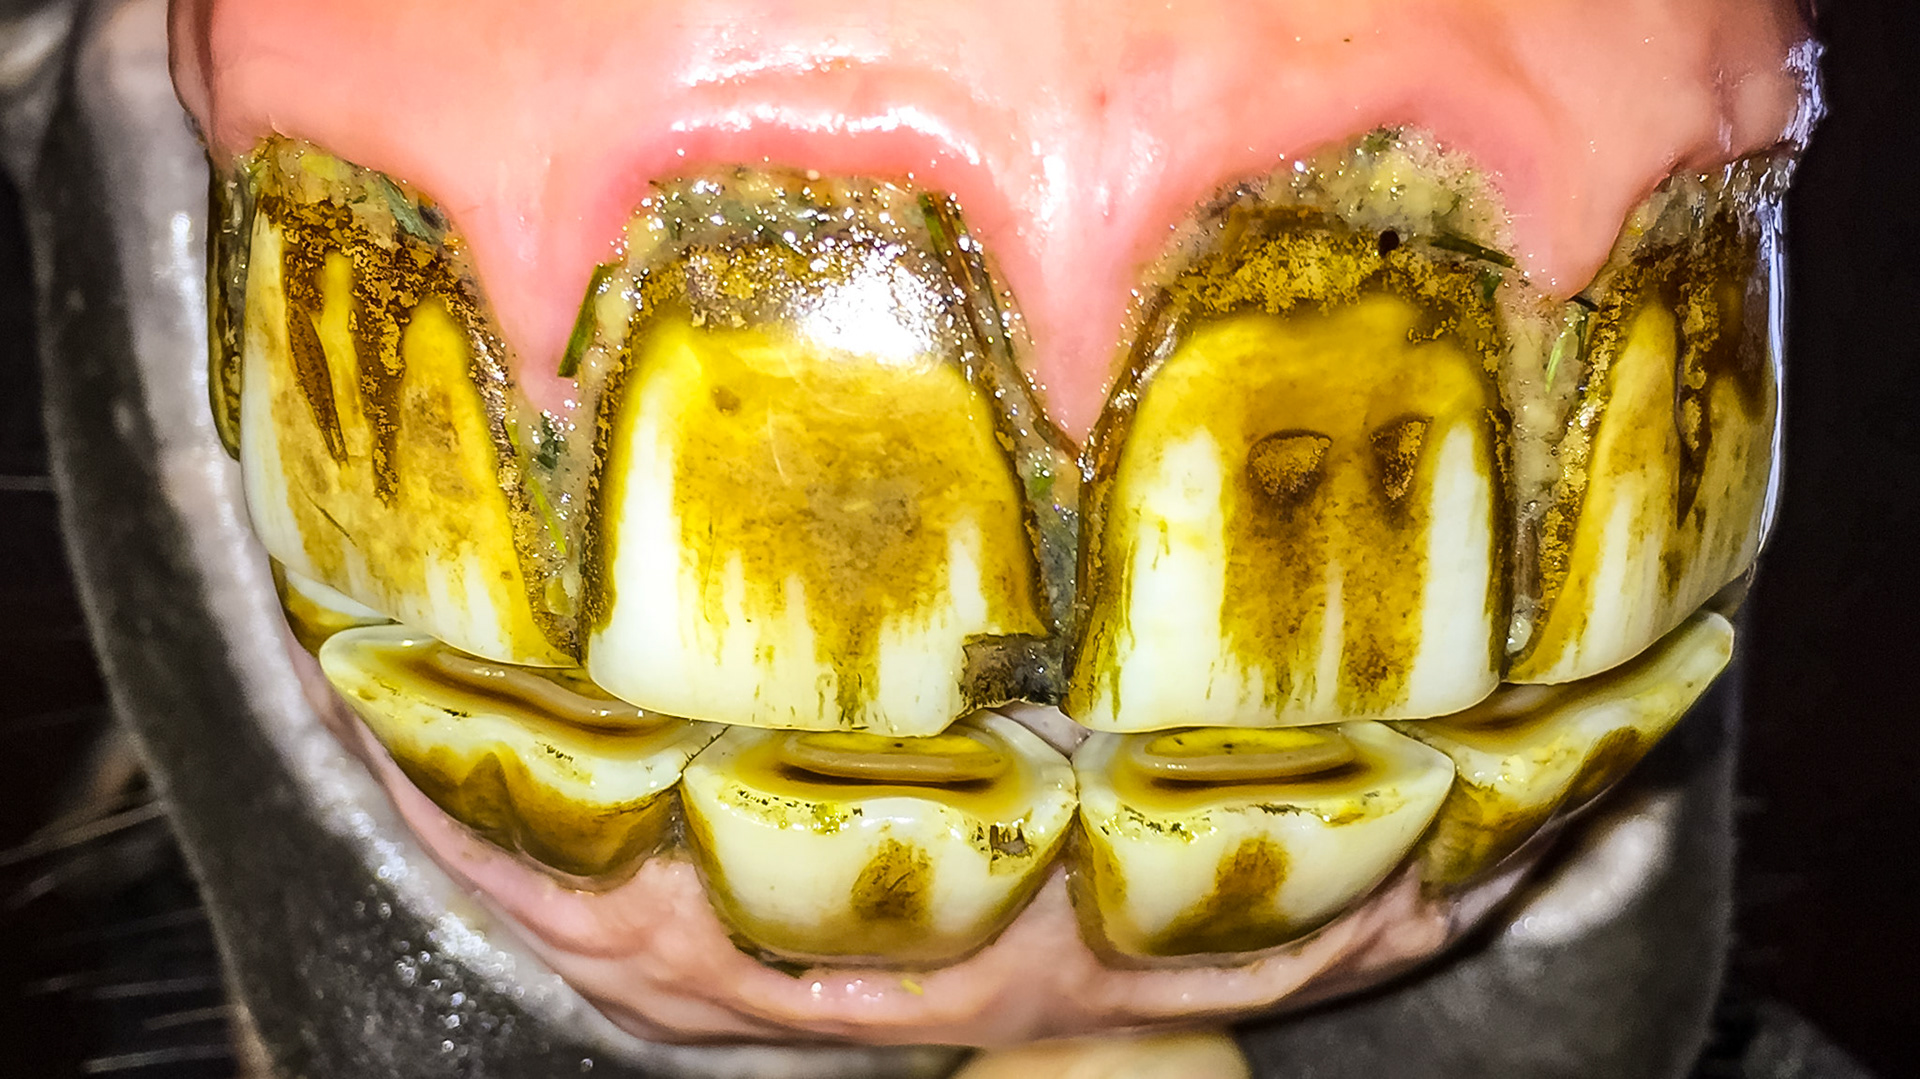

ETORH horse 5 - with loose, painful, & necrotic incisors. Excessive tartar due to tongue not moving over the painful teeth.